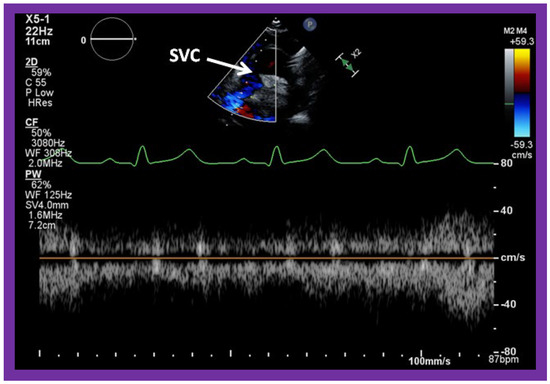

5.3. Echocardiographic Evaluation Following Bidirectional Glenn

Following bidirectional Glenn, the LV size is likely to decrease (normalize) and LV should maintain normal systolic function. This is because of decreased LV volume overload following bidirectional Glenn and the removal of aorto–pulmonary shunt. The 2D imaging of the bidirectional Glenn is difficult to accomplish, but color flow imaging (Figure 25A, Figure 26B, and Figure 27B) from a suprasternal notch or high parasternal views will help image the bidirectional Glenn. Low pulsed Doppler velocity across the superior vena cava (SVC)–PA junction (Figure 25B and Figure 26C) would indicate no obstruction. Turbulent and high velocity Doppler flow suggests the obstruction of the bidirectional Glenn shunt. The size of the branch PAs may be assessed with a combination of 2D and color flow imaging (Figure 26, Figure 27 and Figure 28).

Figure 25. Selected video frames from suprasternal notch view demonstrating bidirectional Glenn shunt; the superior vena cava (SVC) is shown emptying into the right (RPA) and left (LPA) pulmonary arteries by color flow imaging (A). Low Doppler flow velocity across the shunt (B) indicates unobstructed Glenn.